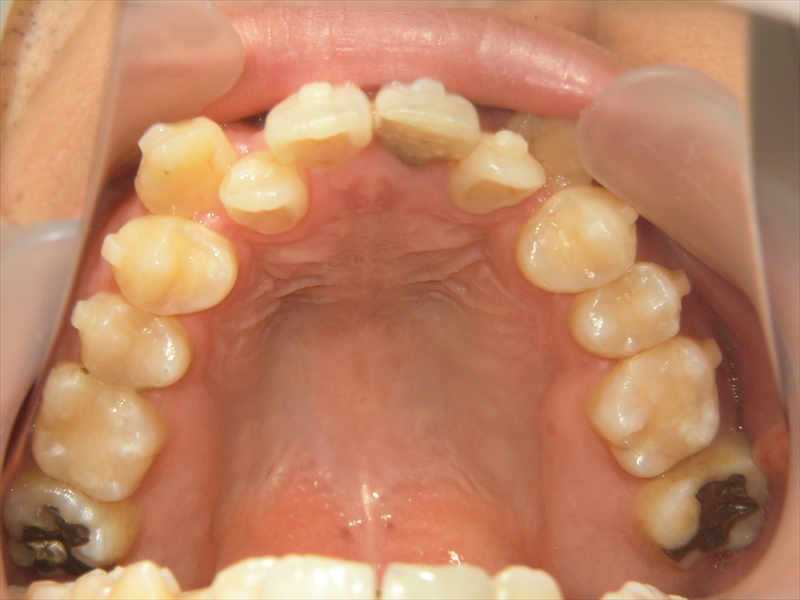

上の歯は歯が並ぶスペースが足りず、八重歯を含むガタガタした歯並びになっていました。

また、歯並び全体がお顔の中心よりも右にずれており、噛み合わせも左右で違っていました。

歯を動かすためのスペースを作る目的で、上の親知らず2本を抜歯し、1本あたりごくわずかに歯を削る処置も行っています。

治療前後 写真